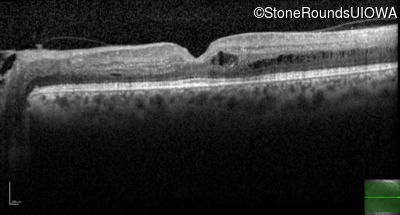

Optical Coherence Tomography - Left - 20/25 -3

Exemplar / OCT Stack

OCT Stack